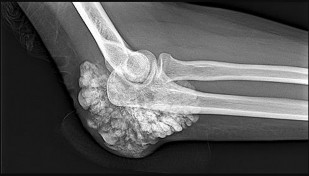

What is the diagnosis?

This patient has a dedifferentiated liposarcoma within a preexisting atypical lipomatous tumor. The imaging demonstrates a large fatty mass with increased internal septations proximally (the atypical lipomatous tumor) and a solid enhancing mass distally (the dedifferentiated portion). A biopsy reveals a high-grade liposarcoma. The other diagnostic responses do not reflect sarcomatous transformation of the lesion.